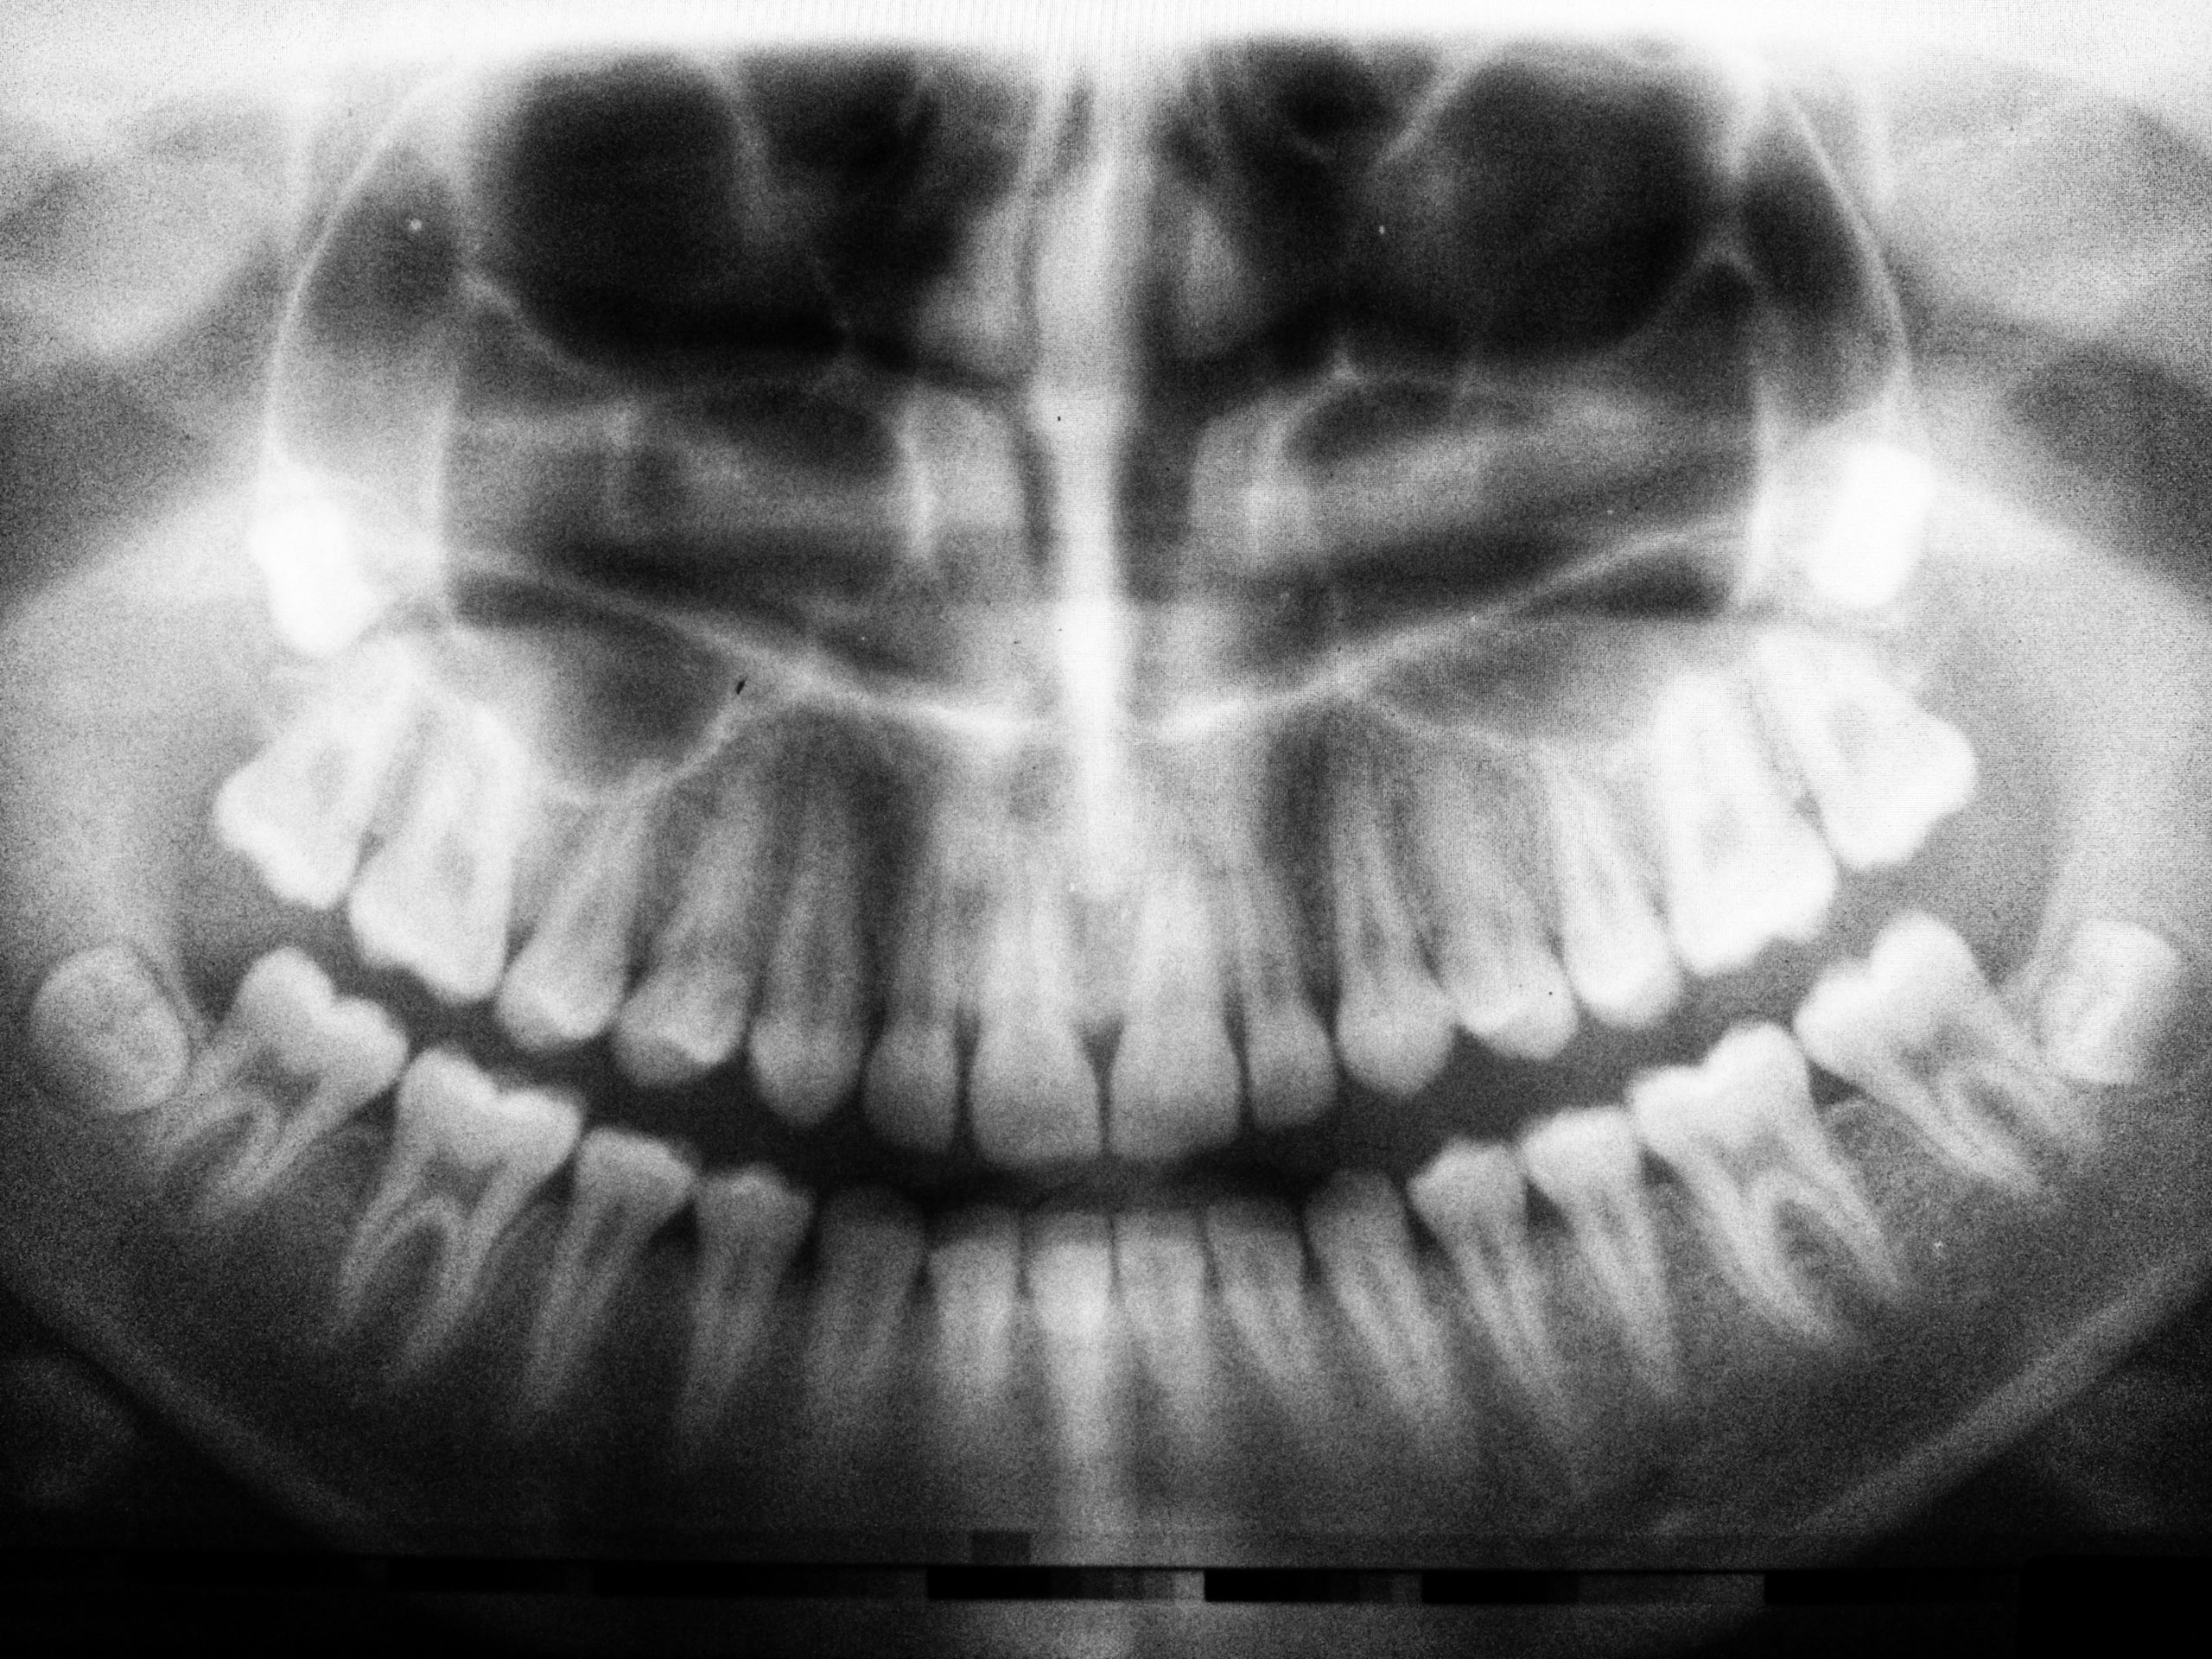

How Safe Are Dental X-Rays?

The use of x-rays is an essential tool in dentistry for the diagnosis of disease and used to guide treatment planning in a safe and logical manner. However, it is understandable that some people may be concerned about the safety of dental x-rays given the use of radiation. In the post, we discuss the safety…